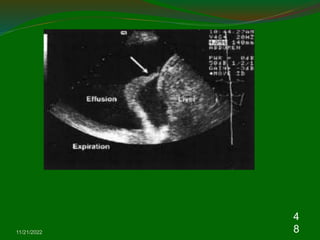

Whereas approximately 500 ml of pleural fluid is

required before an effusion can be identified

clinically, as little 200 ml will blunt the

costophrenic angle.

US in either a standing or sitting position not only

is able to detect smaller volumes of pleural fluid

than the erect frontal chest radiograph but it also

gives useful information about the nature of the

effusion.

The pleural effusion images in ultrasound

appearances are characterized by an echofree

space between the visceral and parietal pleura

.

Pleural effusion.